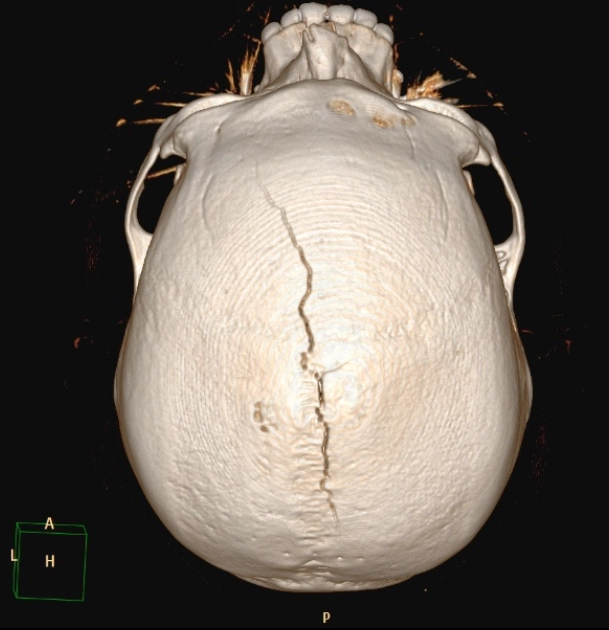

Gãy xương sọ trong tổn thương không do tai nạn (Skull fracture in Non-Accidental Injury - NAI)

16/03/2026